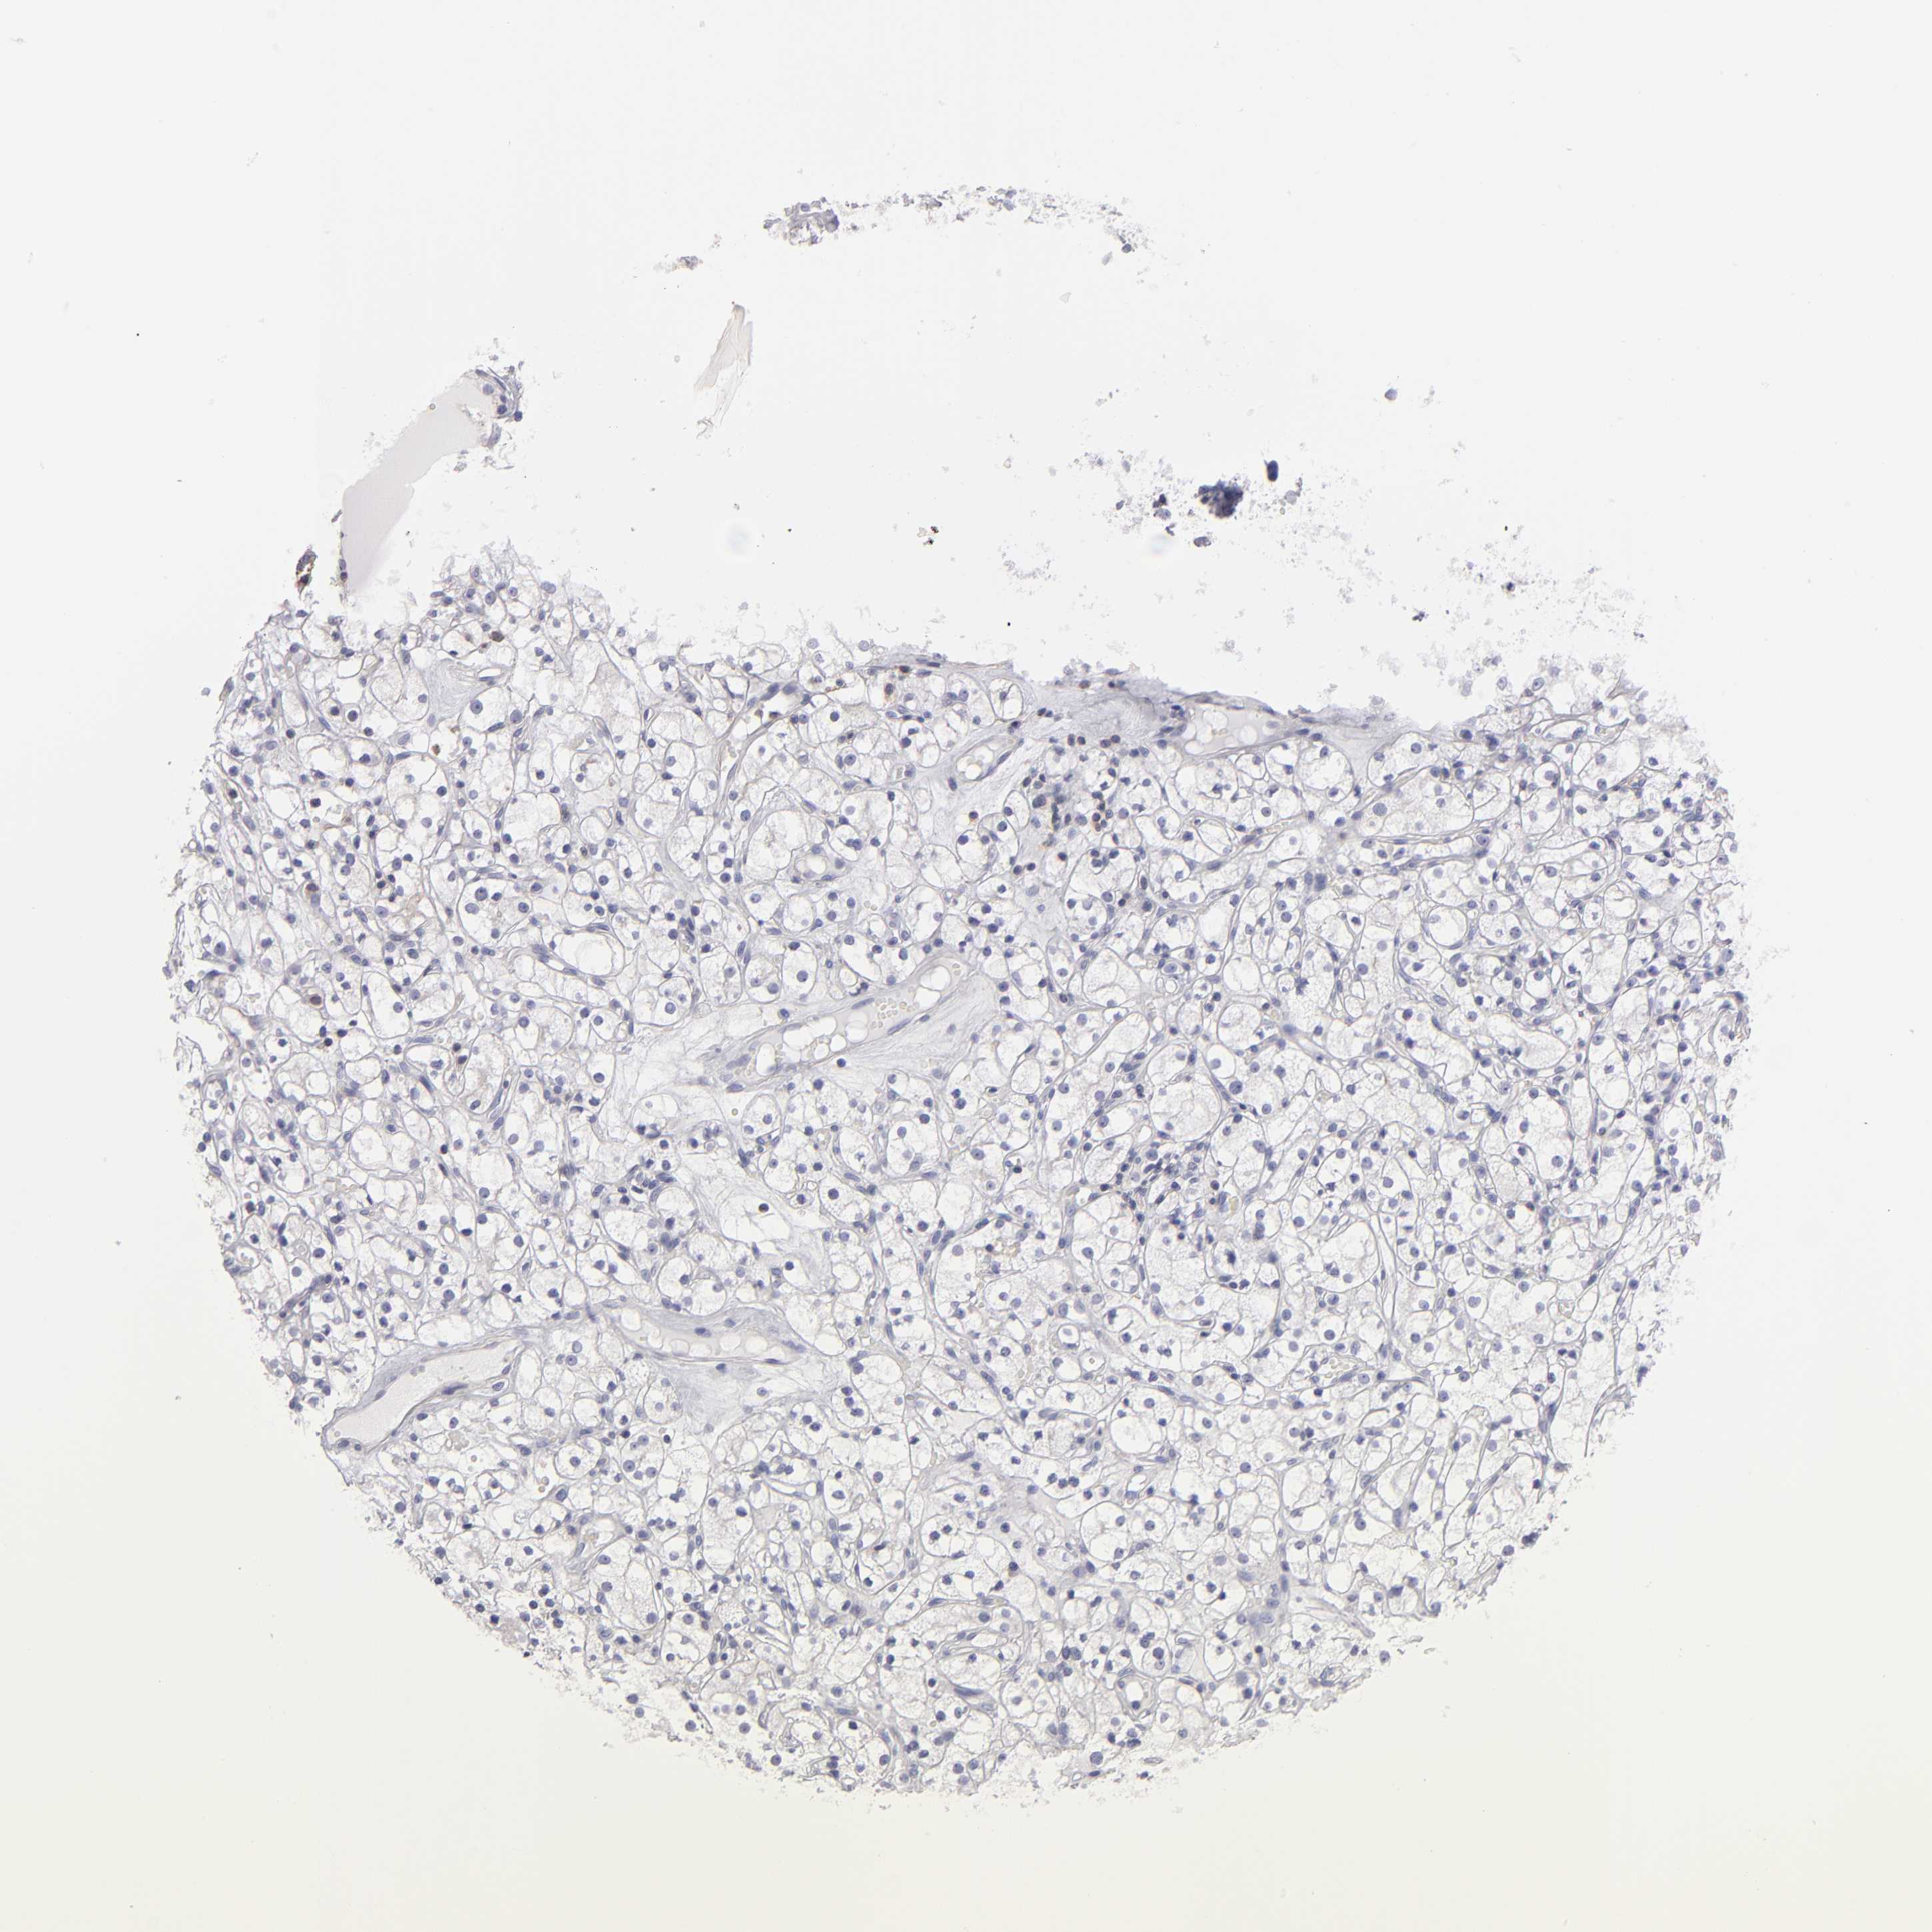

KIDNEY RENAL CLEAR CELL CARCINOMA (VALIDATION) - Interactive survival scatter ploti

The Survival Scatter plot shows the clinical status (i.e. dead or alive) for all individuals in the patient cohort, based on the same data that underlies the corresponding Kaplan-Meier plots. Patients that are alive at last time for follow-up are shown in blue and patients who have died during the study are shown in red.

The x-axis shows the expression levels (FPKM) of the investigated gene in the tumor tissue at the time of diagnosis. The y-axis shows the follow-up time after diagnosis (years). Both axes are complimented with kernel density curves demonstrating the data density over the axes. The top density plot shows the expression levels (FPKM) distribution among dead (red) and alive patients (blue). The right density plot shows the data density of the survived years of dead patients with high and low expression levels respectively, stratified using the cutoff indicated by the vertical dashed line through the Survival Scatter plot. This cutoff is automatically defined based on the FPKM cutoff that minimizes the p-score. The cutoff can be changed by dragging the vertical line or by entering a cutoff value in the square labeled "Current cut-off".

Under the Survival Scatter plot the p-score landscape (black curve; left axis) is shown together with dead median separation (red curve; right axis). Dead median separation is the difference in median mRNA expression between patients who have died with high and low expression, respectively. It is calculated as follows: median FPKM expression of dead patients with high expression - median FPKM expression of dead patients with low expression. This is intended to aid the user in visually exploring custom cutoffs and the associated p-scores and dead median separation.

Individual patient data is displayed and can be filtered by clicking on one or more of the category buttons on the top of the page. Categories describing expression level and patient information include: high, low, alive, dead, female, male and tumor stages. The scale of the x-axis can be toggled between linear and log-scale by clicking on the "x log" button. Mouse-over function shows TCGA ID, patient information and mRNA expression (FPKM) for each patient.

& Survival analysisi

Kaplan-Meier plots summarize results from analysis of correlation between mRNA expression level and patient survival. Patients were divided based on level of expression into one of the two groups "low" (under cut off) or "high" (over cut off). X-axis shows time for survival (years) and y-axis shows the probability of survival, where 1.0 corresponds to 100 percent.

ABCB1 is not prognostic in Kidney Renal Clear Cell Carcinoma (validation)

Best expression cut offi

Based on the FPKM value of each gene, patients were classified into two groups and association between prognosis (survival) and gene expression (FPKM) was examined. The best expression cut-off refers the FPKM value that yields maximal difference with regard to survival between the two groups at the lowest log-rank P-value. Best expression cut-off was selected based on survival analysis .

When clicking on this number, the vertical dashed line indicating cut-off, the interactive survival plot, and the Kaplan-Meier curve will be adjusted to show results based on the best expression cut-off.

: 4.35

Median expressioni

Median expression refers to the median FPKM value calculated based on the gene expression (FPKM) data from all patients in this dataset. When clicking on this number, the vertical dashed line indicating cut-off, the interactive survival plot, and the Kaplan-Meier curve will be adjusted to show results based on the median expression.

: N/A

Median follow up timei

Median follow up time refers to the median time (years) after diagnosis with this type of cancer, based on clinical data from all patients in this dataset.

P scorei

Log-rank P value for Kaplan-Meier plot showing results from analysis of correlation between mRNA expression level and patient survival.

N/A

5-year survival highi

5-year survival for patients with higher expression than the expression cutoff.

For melanoma and glioma, 3-year survival is shown.

5-year survival lowi

5-year survival for patients with lower expression than the expression cutoff.

Average pTPM 22.5

Number of samples 100